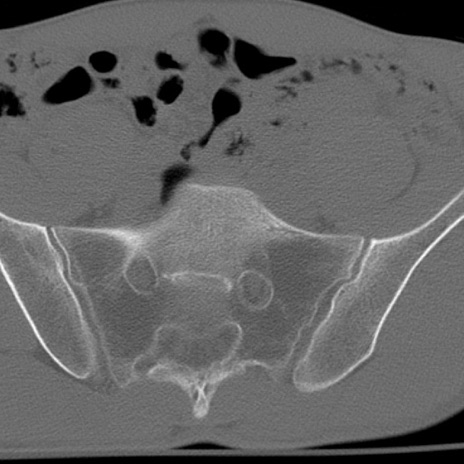

症例3 腰椎CT(横断像)

腰椎CT